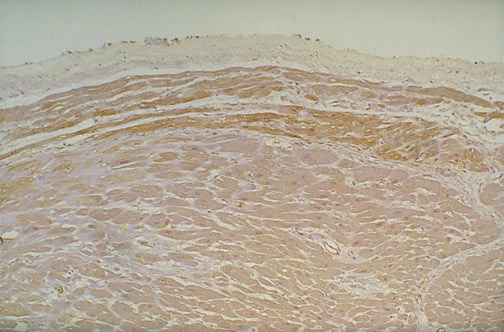

| The cardiac conduction system continues south from the AV node as the bundle of His beneath the endocardium. The more neural features of these fibers is brought out by this S100 immunohistochemical stain, which highlights the bundle of His in longitudinal section. Abnormalities of the conduction system may lead to arrhythmias. |